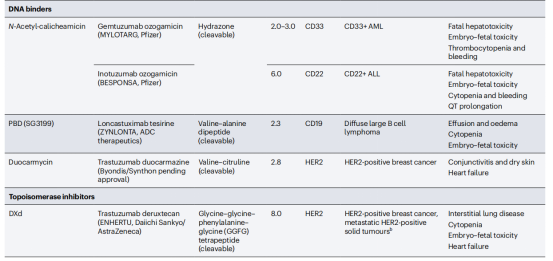

偶联抗体包括抗体药物偶联物(ADC),免疫毒素,放射性同位素相关联的抗体,这些抗体增强了抗体杀死细胞的能力。ADC是通过将肿瘤靶向抗体与细胞毒性药物连接而构建的。ADC分子与细胞表面抗原结合导致其内化,然后在细胞内释放细胞毒性药物。这允许选择性地将细胞毒性药物递送到癌细胞,同时保留大多数健康组织。ADC的关键成分包括肿瘤靶向抗体、细胞毒性药物和连接抗体与细胞毒性药物的连接体。部分ADC药物已显示出显著的临床成功,选择性地向癌细胞递送强效细胞毒性药物。